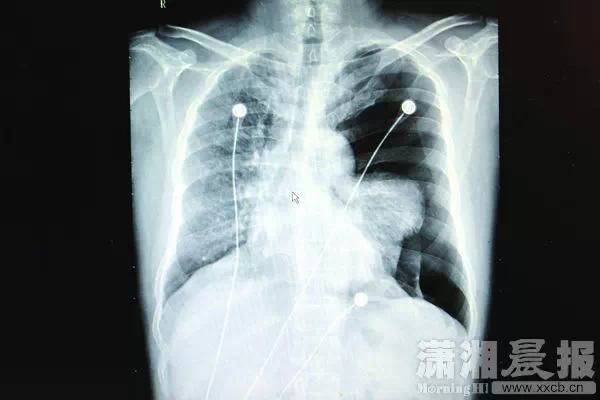

而在2015年1月和2014年8月,还曾有两位男性因为在KTV高音唱歌,分别导致肺大疱破裂、肺部血管破裂,前者甚至导致左肺压缩60%以上,心脏受压移位。